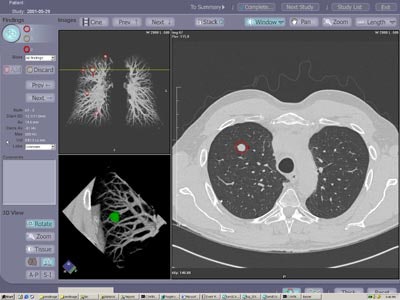

![]() |

| The investigational ImageChecker CT CAD software is designed for the early detection of clinically significant lung nodules in CT. The CAD algorithm highlights potential areas of interest and provides measurement and characterization information on detected lesions. Image courtesy of R2 Technology. |

CAD improves both reading times and sensitivity for all readers, Schoepf said. Moreover, CAD improved the results of less-experienced readers to the point where they were comparable to those of far more experienced readers, he concluded.